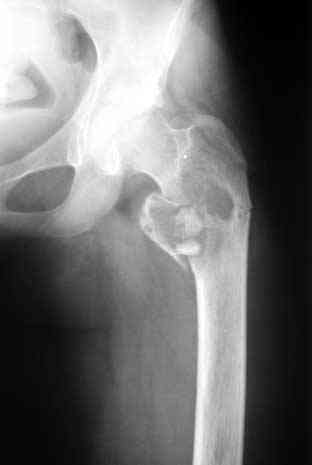

Согласен на все сто с Вашей последней фразой. Не знаю как учат сейчас врачей в ВУЗАХ, но по-моему основы доказательной медицины познаются уже в процессе работы. А что касается Вашего примера, то давно известно, что кистозные опухоли у детей могут спонтанно регенерировать после перелома. Пример рецидива кисты после неадекватной пластики Вы видите на этой же странице. По поводу РФ не могу судить, но в Казахстане больше применяют стоматологи для подготовки к импланатации протезов при дефектах костей челюсти. Спасибо за обсуждение темы.